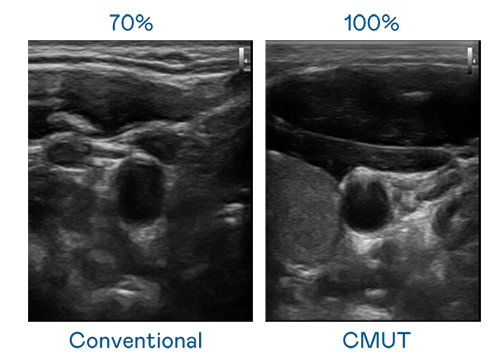

CMUT 技术是一种用电容式微机电元件来产生超音波讯号的技术。与传统 PZT 压电式技术相比,CMUT 频宽增加 30%,更宽频的超音波讯号让影像解析度大幅提升,是实现高影像品质医疗超音波扫描、促进精准医疗发展的关键技术。

超音波影像的解析度高低,首先取决于探头能发出的讯号频宽。尊龙人生就是博首页 CMUT 可提供高清晰的超音波讯号,提供高频宽、高灵敏度、影像纹理细节更高的超音波影像,协助医护人员缩短影像判读时间及利用精准的医疗影像进行诊断。